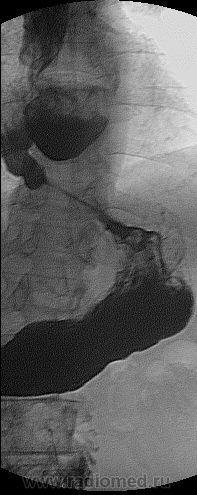

Мой коллега после МСКТ-ОГП, решил почему то о наличии фиксированнай грыжи диафрагмы, пациент попал ко мне на R-скопию пищевода и желудка:

Что скажешь, отличная демонстрация – редкий дивертикул. КТ-ушечник наверное, имел в виду фиксированную грыжу ПОД. А желудок-то на месте. Приятно поправить коллегу нетрадиционной ориентации. Но, конечно, этот случай для них труден: они видят статичную картину – чистую анатомию. А тут важна динамика, физиология нам помогает.

Какой большой диверитул в пищеводе. Вы не производите прицельных снимков, а только большие. Эти снимки сделаны не во время рентгеноскопии, да?

А почему для исследования пищевода Вы не используете сметанообразный или пастообразный барий.

А ниже дивертикула слизистая пищевода ненормальная.

v1tal: спасибо за публикацию КТ! По моему скромному мнению; наличие дивертикула не вызывает сомнений, то что описали как диафрагмальная грыжа-это врачебная ошибка.

Пациент поступил в стационар(отеделение терапии) с Ds: Внегоспитальной правосторонней пневмонией. После того как мой коллега описал при поступлении цифровые R-граммы ОГП, отметив о наличие фиксированной грыжи пищеводного отверстия дифарагмы(под вопросом), клиницисты сразу направили пациента на КТ с предворительным обоснованием: пневмония, абсцесс, ГПОД? И только спустя через 3-4 дня после МСКТ, как только пациент был прокунсультирован хирургом, его направили ко мне на R-скопическое исследование. МСКТ-делалось только один раз.

Окончательно о дивертикуле, конечно было выставлено, после проведения R-скопии. Но я ещё раз хочу повториться, что абсолютно все коллеги которые занимаются КТ, они не считают серьездным данный метод по отношению к ноовобразованию ЖКТ, я пытался объяснить, после ряда некоторых случаев с анализом МСКТ, что не обязательно впринципе проводить R-скопию, когда всё и так ясно, но меня посмотрели "косо".